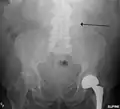

-

Aortic measurement on abdominal ultrasonography in the axial plane between the outer margins of the aortic wall[39] -

Ultrasonography in the sagittal plane, showing axial plane measure (dashed red line), as well as maximal diameter (dotted yellow line), which is preferred -

A ruptured AAA with an open arrow marking the aneurysm and the closed arrow marking the free blood in the abdomen -

Sagittal CT image of an AAA

Biomechanical AAA rupture risk prediction -

An axial contrast-enhanced CT scan demonstrating an abdominal aortic aneurysm of 4.8 by 3.8 cm -

The faint outline of the calcified wall of an AAA as seen on a plain X-ray -

Abdominal aortic aneurysms (3.4 cm)